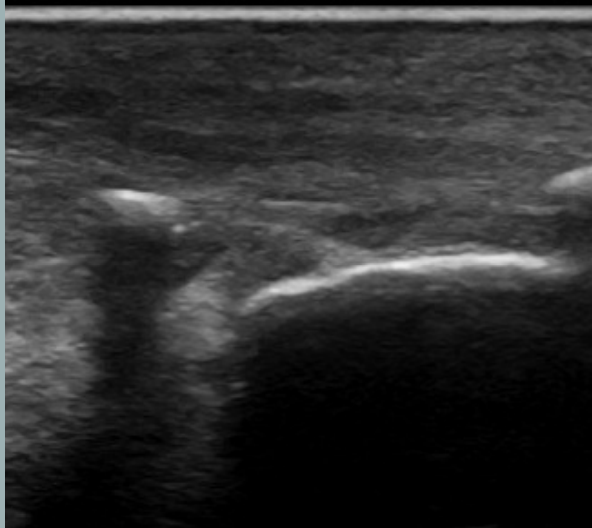

Sombra acústica

- Las ondas de sonido no pueden atravesar una estructura densa (material mineral) o un estrato de gas.

- La imagen generada presenta una línea superficial hiperecogénica que describe la superficie de la estructura, a partir de la cual, pierdo completamente la visualización de los estratos profundos (región oscura).